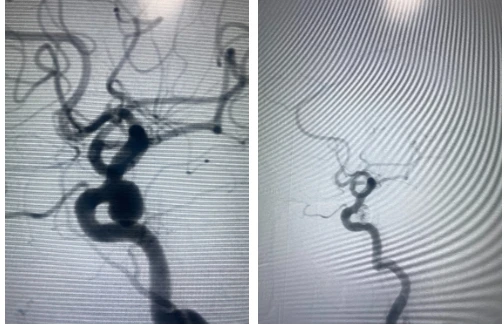

Mạch máu não sau khi được can thiệp. Ảnh: BVCC |

Tại đây, sau khi thăm khám và chụp CT, các BS phát hiện túi phình mạch não có kích thước lớn, cổ túi phình rộng, vị trí tại động mạch cảnh trong trái. Các BS quyết định dùng phương pháp stent-coil để điều trị. Đây là phương pháp mới, hiện đại và hiệu quả cao.

Sau khi can thiệp, sức khỏe bà T ổn định, hết đau đầu.